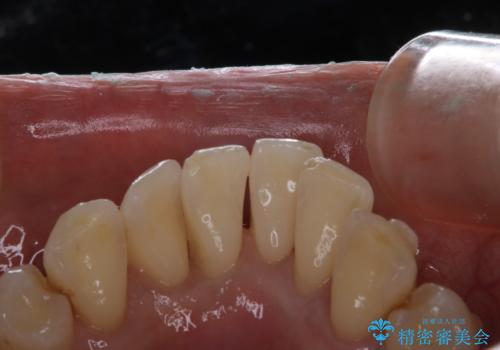

マウスピース矯正インビザライン治療では、歯の表面にアタッチメントという突起を設定します。(アタッチメントは歯の動きを効率的に移動するためのものです)

アタッチメントが歯に付くと、表面が凸凹し磨き残しが多くなったりと、プラークや歯石・着色がつきやすくなることがあります。

矯正治療中もPMTCを定期的に行い、専門的な機械でしっかりと汚れを除去することがおススメです。